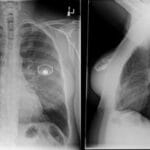

- Radiology Cases: Images with a to-the-point discussion highlighting the specific diagnostic criteria.

- Radiology Case of the Day Collection: Aunt-Minnie Board Cases for Rapid Review.

- Radiology Spotters: 700+ spot / “Aunt-Minnie” cases divided into sets of 10 each!